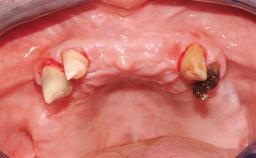

| Case Type | Extended Space |

| Jaw | Maxilla |

| Area | Anterior |

| # of Teeth | 4 |